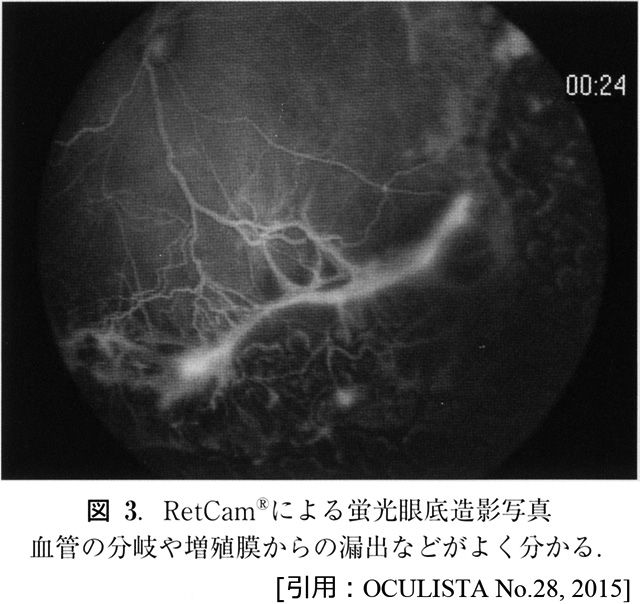

最周辺部の無血管領域に接する(有血管先端部)毛細血管の異常分岐・増殖(血管新生).

これにより増殖部が明瞭化,硝子体側へ隆起.「境界線」という.

既存網膜血管の拡張.

硝子体内への滲出反応,出血.